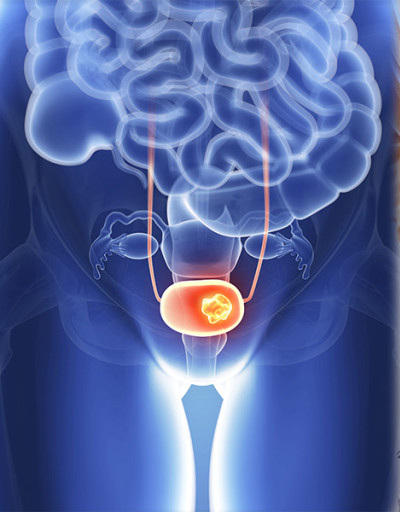

전립선암이란?

전립선에서 발생하는 암을 말하며, 대부분 전립선 세포에서 발생하는 샘세포의 암입니다. 기능에 고장이 생긴 세포는 죽지 않고 종괴를 형성할 수 있습니다. 이 종괴는 양성 종양과 악성 종양으로 나뉘는데, 전립선암은 악성 종양입니다. 참고로 전립선비대증은 양성 종양입니다.

10. 전립선암 뼈전이

전립선암은 뼈로 잘 전이됩니다. 전립선암이 뼈로 전이되면 전이된 부위에서 통증이 발생하게 되며, 그 부위가 약해지면 골절이 생길 수도 있습니다. 전립선암 뼈전이는 주로 골반뼈, 요추, 흉추 등으로 전이되는 그럴 경우가 많습니다.